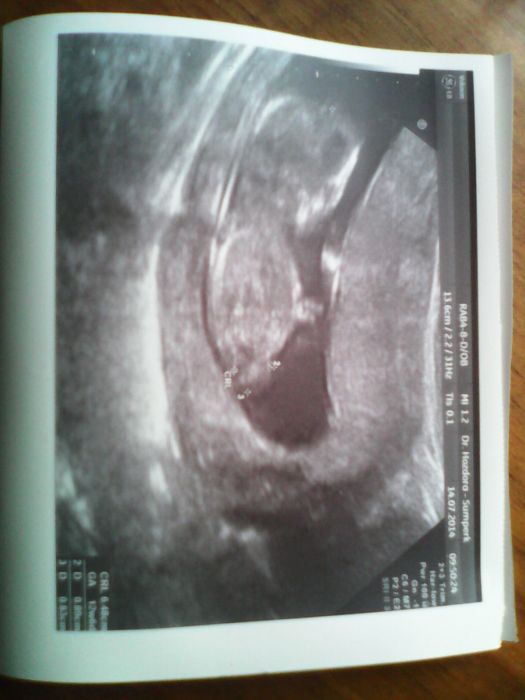

Děvčata zdravím,hlásím dnes jsem 12+2tt,dle ultrazvuku 12+6tt. Jsme obříci,máme už 8,2cm. Mimčo bylo celou dobu akční,krása. Další poradnu mám 7.8. Sestra mi vzala preventivně krev na boreliozu,kvůli těm klíštákům,co jsem si před měsícem donesla z lesa. Taky mi dělal lékař preventivní prohlídku,tak doufám,že stěry a odběr dopadne na výbornou a bude vše v pohodě jako doposud. Ali,přeji si holčičku,můj chlap by radši kluka,ale já nějak cítím,že to bude holka.....však uvidím zítra,kdy jdu na prvotrimestrální screening. Přikládám fotečku.

[591057] gratulace velka,krasna fotecka

[591057] Janulko to je krásná holčička. A roste jak z vody. Musi to byt štěstíčko , koukat jak se na ultrazvuku hýbe. To to, že jste obříci je jasne, když už maminka byla zrychlená ;-). Tak držím palečky na ten screening ;-)